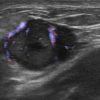

Ung thư vú

Ung thư vú - Ảnh 3

» Thông tin: Nữ giới – 54 tuổi.

» Lâm sàng: Khối tuyến vú.